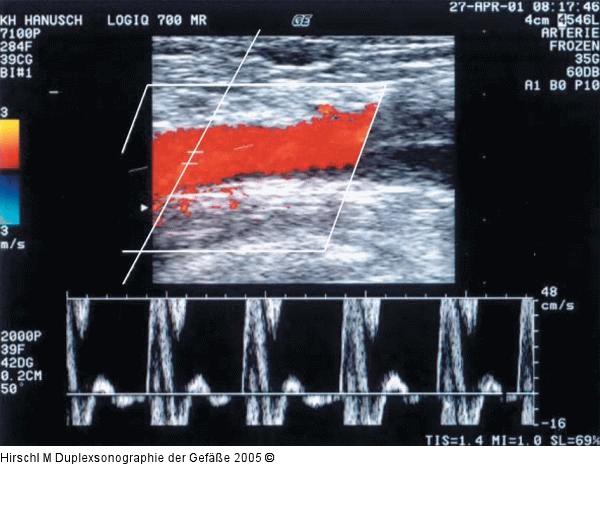

Abbildung 16: Duplexsonographie - Pulsdoppler

Schlecht eingestellte Dopplerfrequenzskalierung mit sowohl systolischem (die "abgeschnittene Systole" ist unter der Nulllinie wieder zu sehen) als auch diastolischem Alias-Effekt (der abgeschnittene maximale diastolische Flußanteil ist als "verkehrte Spitze" am Oberrand des Dopplerspektrums zu sehen). Weitere Einstellungsfehler beinhalten ein zu gering gewähltes Meßvolumen, ein übersteuertes Farbgain sowie eine Übersteuerung der Empfangsverstärkung des B-Bildes (zu weiche und zu verschwommene Strukturen im BBild). |